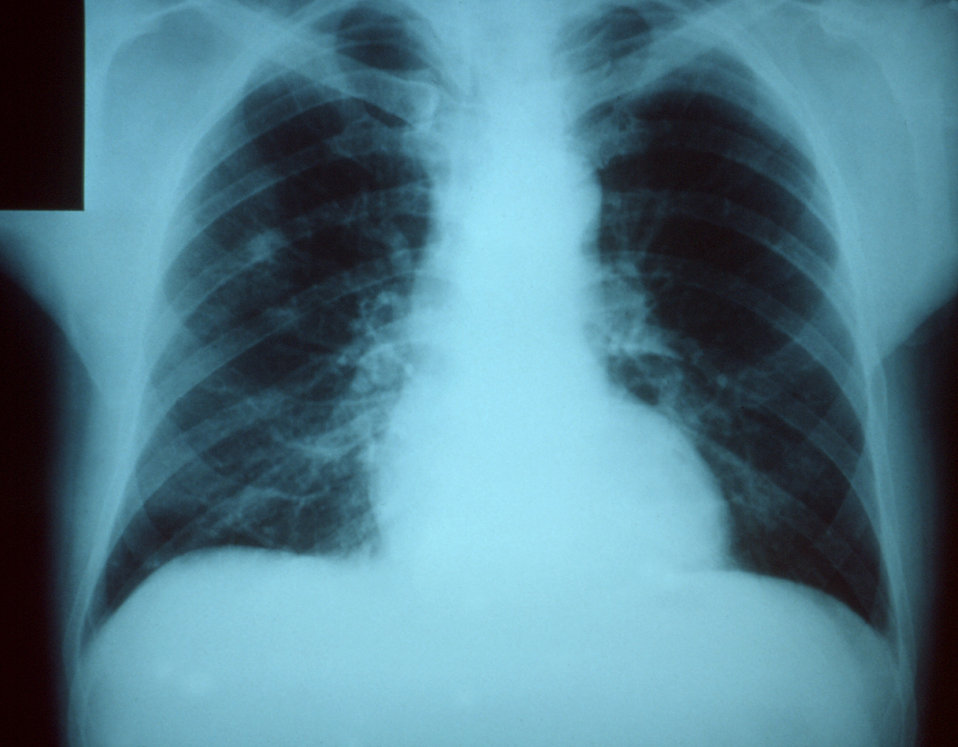

Pneumonia

Pneumonia, a bacterial infection of the lungs, also known as ‘Winter Fever’, was a great concern in colonial Virginia. Although it was not known as a disease in and of itself but rather a symptom of other illnesses until much later, the presence of this respiratory ailment was noted by colonists.

Pneumonia and many other such illnesses were prevalent in the winter months when conditions forced people inside with closed windows and doors. Prior to modern home climate-control technology, windows and doors were opened in good weather to create a breeze that cooled down a house but also served to air it out. Additionally, many activities we perform indoors today took place outside, such as laundry and food processing, which got people out in the open more. When the weather turned cold, however, people were stuck inside with little ventilation and essentially stewing in their own germs. As such, pneumonia spread rampantly throughout the winter, and with no antibiotics, it was often deadly especially for the young and elderly.